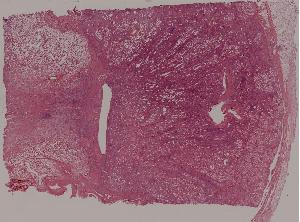

36.恶性淋巴瘤